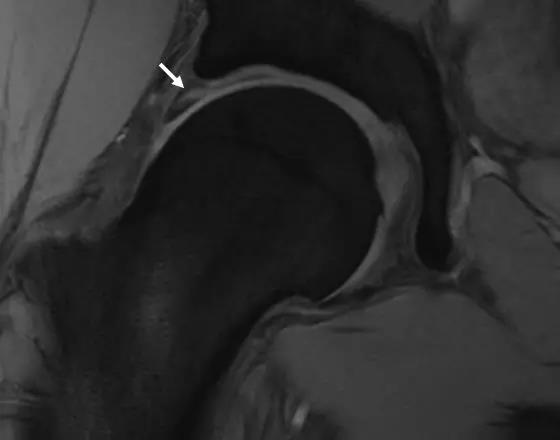

MRI表现

- 基本表现同X线。

- 对髋臼盂唇和软骨损伤的检出有较高的敏感性和特异性。

- 其它表现:

- 股骨颈疝窝

- 关节积液及滑膜增生

- 骨髓水肿MR造影优于常规MR

- 股骨头颈联合处前上缘骨性突起。

- 凸轮撞击型FAI--并盂唇撕裂。